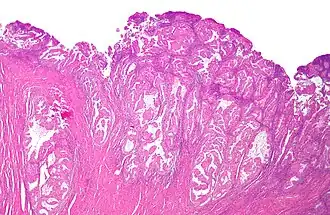

Coupe histologique d'un adénocarcinome endométrioïde, la forme la plus fréquente de cancer de l'endomètre. Coloration à l'hématoxyline et à l'éosine.

Les carcinomes de l'endomètre sont de plusieurs types histologiques : l'adénocarcinome endométrioïde est le plus fréquent (75 à 80 % des cas[7]), suivi du carcinome mixte (10 %), de l'adénocarcinome séreux (moins de 10 %, de mauvais pronostic et qui se traite comme un cancer de l'ovaire). Seule la forme endomètioïde est sensible aux hormones. L'adénocarcinome non endomètrioïde se voit plus fréquemment chez l'afro-américaine, avec un plus mauvais pronostic[7].